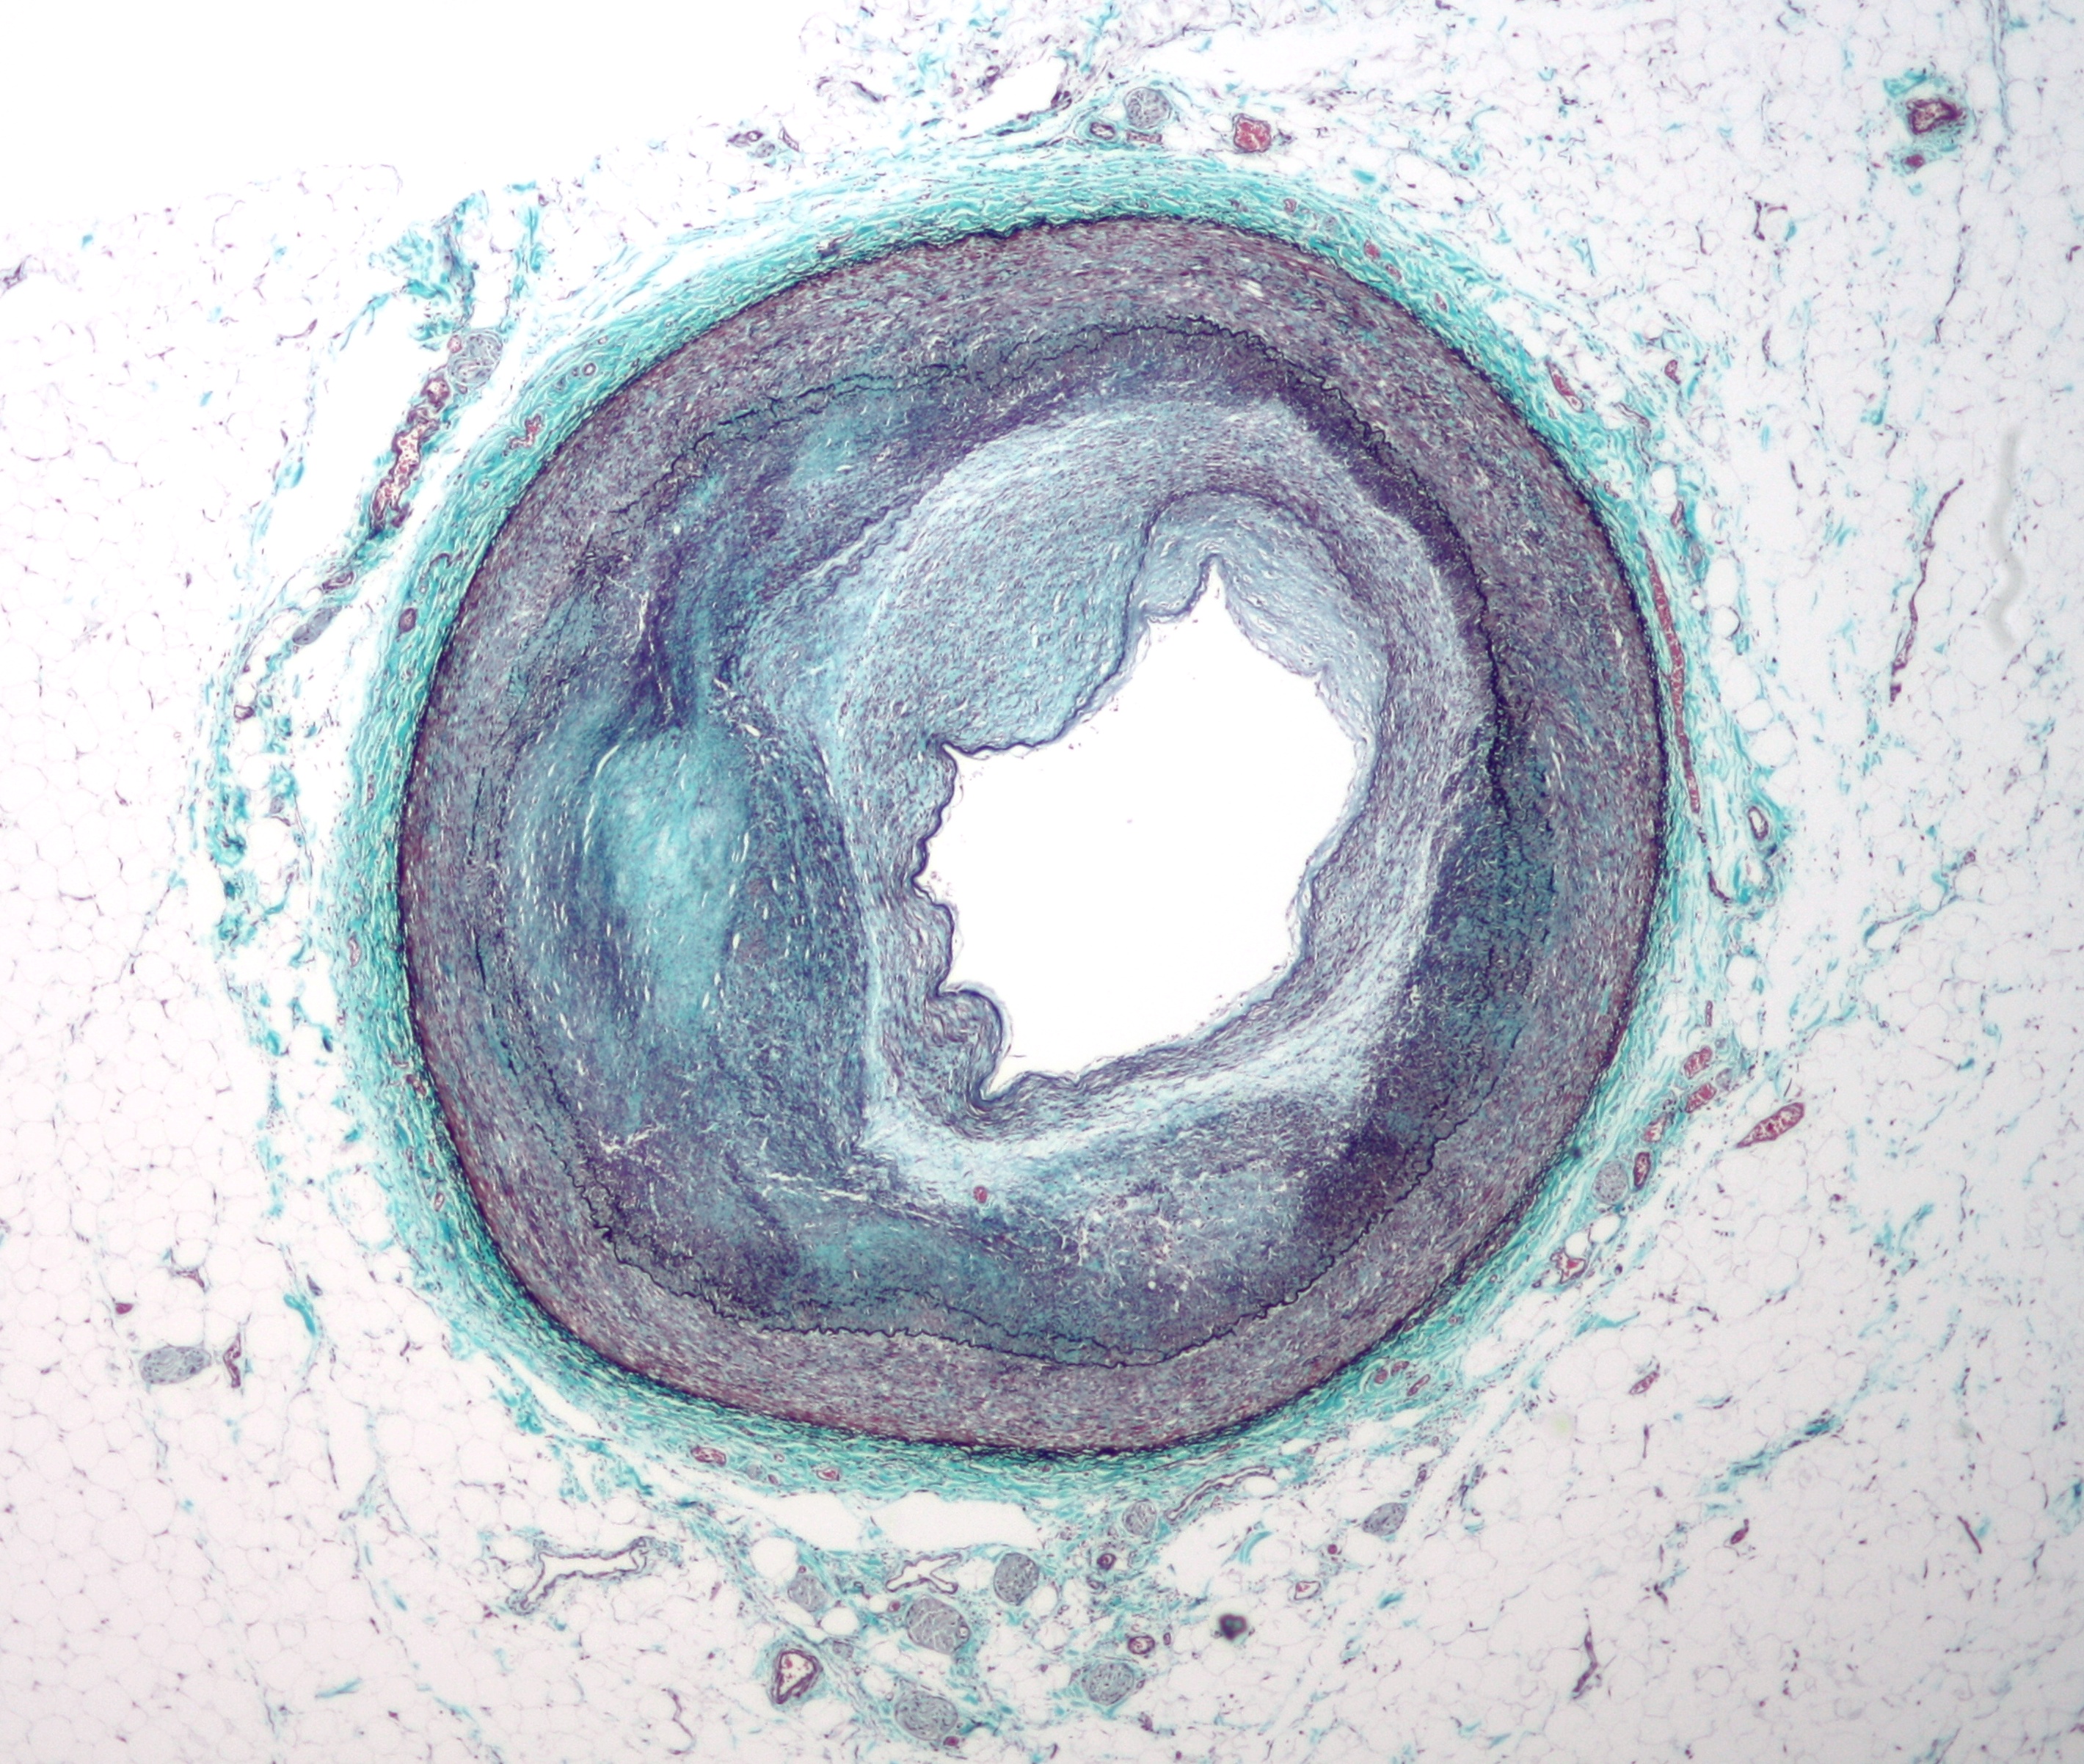

동맥은 일반적으로 현미경으로 연구되지는 않지만, 다음 두 가지 플라크 유형을 구별할 수 있다.[70]

- 섬유지질 플라크는 동맥의 내막 아래에 지질이 풍부한 세포가 축적되는 특징이 있다. 일반적으로 동맥벽의 경계 근육층이 보상적으로 확대되어 내강이 좁아지지는 않는다. 내피 아래에는 플라크의 죽상"핵"을 덮는 "섬유 캡"이 있다. 핵은 지질이 풍부한 세포(대식세포 및 평활근 세포)로 구성되어 있으며 조직 콜레스테롤과 콜레스테롤 에스터 함량, 피브린, 프로테오글리칸, 콜라겐, 엘라스틴, 세포 잔해가 증가한다. 진행된 플라크에서는 플라크의 중앙 핵에 일반적으로 세포 외 콜레스테롤 침착물(사멸한 세포에서 방출됨)이 포함되어 빈 바늘 모양의 틈이 있는 콜레스테롤 결정 영역이 형성된다. 플라크의 주변에는 더 젊은 "거품" 세포와 모세 혈관이 있다. 이러한 플라크는 파열될 때 일반적으로 개체에게 가장 큰 피해를 준다. 콜레스테롤 결정도 역할을 할 수 있다.[71]

- 섬유 플라크는 내막 아래, 동맥벽 내에 국한되어 벽의 비후 및 확장을 유발하며, 때로는 근육층의 위축과 함께 국소적인 내강 협착을 유발한다. 섬유 플라크에는 콜라겐 섬유(호산성), 칼슘 침전물(헤마톡실린성), 드물게 지질이 풍부한 세포가 포함되어 있다.

동맥벽의 근육 부분은 존재하는 죽상종을 담을 수 있을 정도로 충분히 큰 작은 동맥류를 형성한다. 동맥벽의 근육 부분은 죽상 플라크를 보상하기 위해 재형성된 후에도 일반적으로 강하게 유지된다.

그러나 혈관벽 내의 죽상종은 부드럽고 탄성이 거의 없어 부서지기 쉽다. 동맥은 각 심장 박동, 즉 맥박에 따라 끊임없이 팽창하고 수축한다. 또한, 죽상종의 외부 부분과 근육벽 사이에 진행되면서 칼슘 침착이 발생하면 전체 동맥의 탄성이 손실되고 뻣뻣해진다.

5. 병태 생리

죽상 발생은 죽상 반의 발달 과정이다. 이는 동맥의 재형성을 특징으로 하며, 반이라고 불리는 지방 물질이 내피 하 공간에 축적된다. 죽상 반의 형성은 동맥벽 내에서 그리고 여러 국소 혈관 순환 인자에 대한 반응으로 발생하는 복잡한 일련의 세포 사건을 통해 수년에 걸쳐 발달하는 느린 과정이다.[63] 이러한 병변의 대부분은 과도한 지방, 콜라겐 및 엘라스틴으로 구성된다. 처음에는 반이 커지면서 협착 없이 벽 두께만 증가한다. 협착은 후기 사건이며, 결코 발생하지 않을 수도 있으며, 단순히 죽상 경화 과정뿐만 아니라 반복적인 반 파열 및 치유 반응의 결과인 경우가 많다.[64]